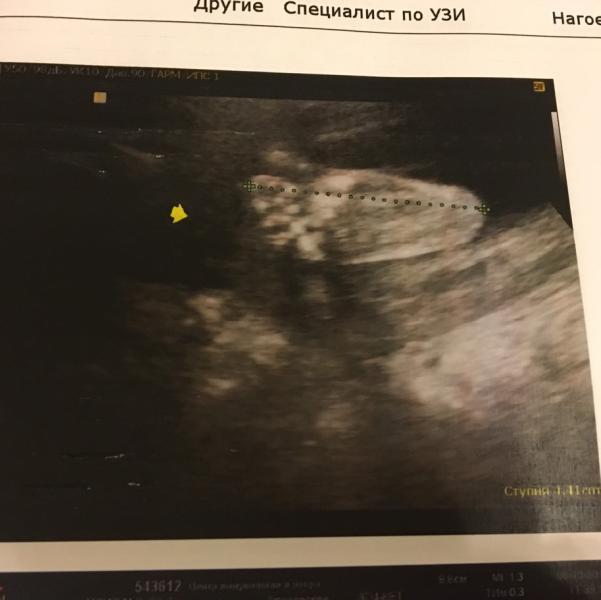

Попала я к Нагоевой Т.И. Замечательный специалист, грамотный и серьёзный. Смотрит все досконально, внимательно, буквально каждый сантиметр. Каждое действие комментирует так, что понятно было и мне, и папе:) отметает все возможные риски один за другим, поэтому с каждой минутой становится спокойней и счастливей:) А ещё, у неё много повышений квалификаций и она специализируется на УЗД сердечно-сосудистой системы, патологиях и отклонениях, так что если есть сомнения, то она поможет разобраться. И ещё, кто сомневается, делать УЗИ в 24-25 недель или подождать, то можно делать! Все уже отлично видно, и моську, и все органы, и думаю не менее интересно, чем в недель 30-32.

Добавляю фото наших сладких пяточек, и желаю всем девочкам малышей, здоровеньких с первого дня их жизни в животике!